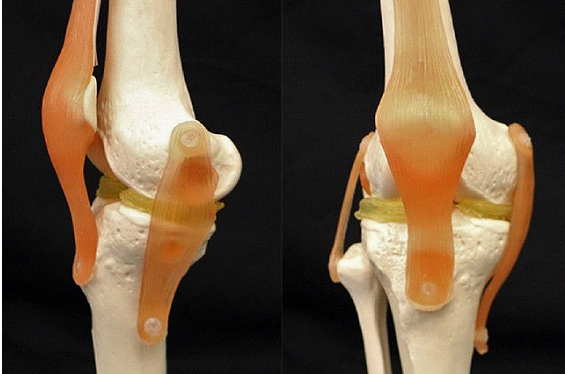

At present, the team members have demonstrated the feasibility of the 3D-printed material using a plastic knee model. In their demo, they scanned this model and then used their double-network hydrogel material to create a 3D model of the menisci. Impressively, the process took just one day to complete.